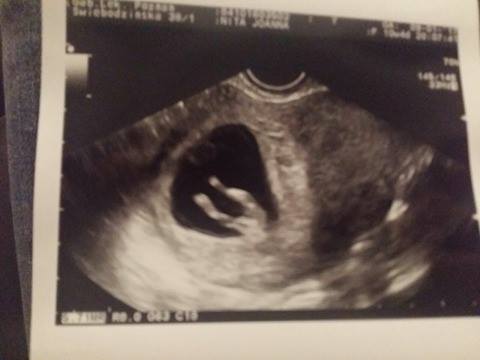

Cześć Kochane. Po powrocie do pracy mam dużo mniej czasu na regularne odwiedzanie forum i widzę, że mam sporo zaległości. Ja była dziś na USG i wszystko super. Maleństwo bardzo się ruszało więc ciężko było zrobić zdjęcie, ale doktor była bardzo zadowolona i mówiła, że wszystko ok.

Hihi, na pierwszym zdjęciu wygląda jak kosmita [emoji89] [emoji106]Cześć Kochane. Po powrocie do pracy mam dużo mniej czasu na regularne odwiedzanie forum i widzę, że mam sporo zaległości. Ja była dziś na USG i wszystko super. Maleństwo bardzo się ruszało więc ciężko było zrobić zdjęcie, ale doktor była bardzo zadowolona i mówiła, że wszystko ok.

Zobacz załącznik 790873 Zobacz załącznik 790872 Zobacz załącznik 790871